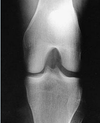

The bone part identified in the figure attached is the:

a. lateral condyle

b. medial condyle

c. lateral malleolus

d. medial malleolus

lateral malleolus